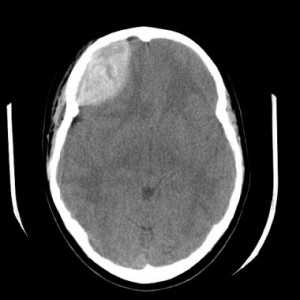

Эпидуральная гематома (экстрадуральная гематома) имеет травматическое происхождение. Это скопление крови внутренний костной пластинкой и твердой мозговой оболочкой. Обычно гематома расположена под областью перелома костей черепа. Причиной кровоизлияния является разрыв оболоченной артерии. Встречаются эпидуральные гематомы вдвое реже субдуральных. По форме гематома двояковыпуклая. Чаще всего диагностируется в неотложных условиях методом КТ. МРТ обычно применяется при спинальных эпидуральных гематомах.

![КТ - эпидур гематома]()

КТ. Эпидуральная гематома.